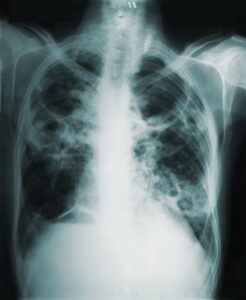

1. Breathing Difficulty

-

Fast breathing

Difficulty breathing in children is an important warning sign that requires medical attention. -

Chest pulling inwards (retractions)

Grunting sounds

Severe wheezing

Bluish lips or face

┬а Breathing distress is always an emergency.